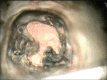

Successful endodontic treatment relies upon a thorough knowledge of root canal anatomical variations along with proper diagnosis, treatment planning, and clinical expertise. One of the difficult root canal configurations that are frequently encountered commonly in mandibular second molars is C-shaped root canal. Due to the intricate root canal configuration, it is often difficult to negotiate, debride, and obturate such canals leading to failure of root canal treatment. Understanding the anatomical variation and adequate visualization will enable the clinician to manage these cases effectively. Advanced irrigation and obturation techniques help in managing such anomalous canal configurations. This article presents the management of two different C-shaped root canal configurations under dental operating microscope using thermoplasticized obturation techniques.